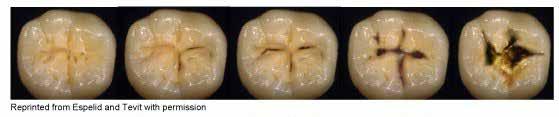

earn up to 6 hours of general continuing education (CE) by reading the Diagnostic Discussion column included in the bi-monthly Today’s FDA and taking a quick online quiz